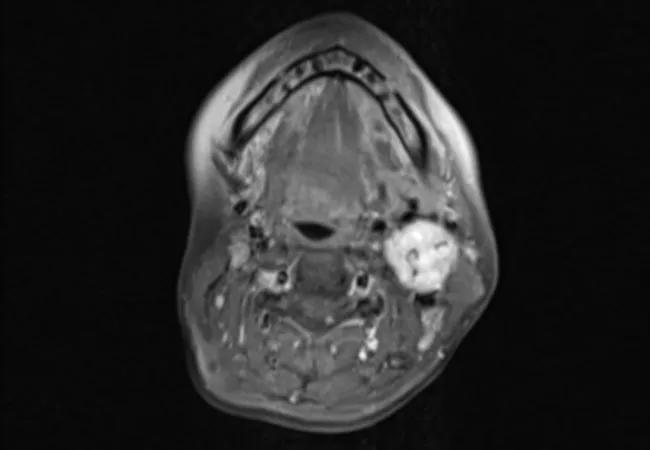

In one of the largest cohort studies of head and neck paragangliomas, study authors characterize the incidence of tumor recurrence after treatment. The study provides new insights about the risk of disease progression and offers new surveillance recommendations.

The retrospective cohort study examined 173 adults with 189 paragangliomas (41.3% carotid body, 47 29.1% glomus jugulare, 19.0% glomus tympanicum, and 10.6% glomus vagale) who received treatment between 1990 and 2010.

Results showed that glomus jugulare tumors were more likely to recur after initial treatment (HR = 3.69, 95% CI: 1.70-8.01, P < .001), while carotid body tumors were comparatively less likely to occur (HR = 0.44, 95% CI: 0.21-0.97, P = .041). Importantly, the study also found that carotid body tumors had lower risk of recurrence with surgery compared to radiation, while globus jugulare tumors showed a lower risk of recurrence with radiation compared to surgery.